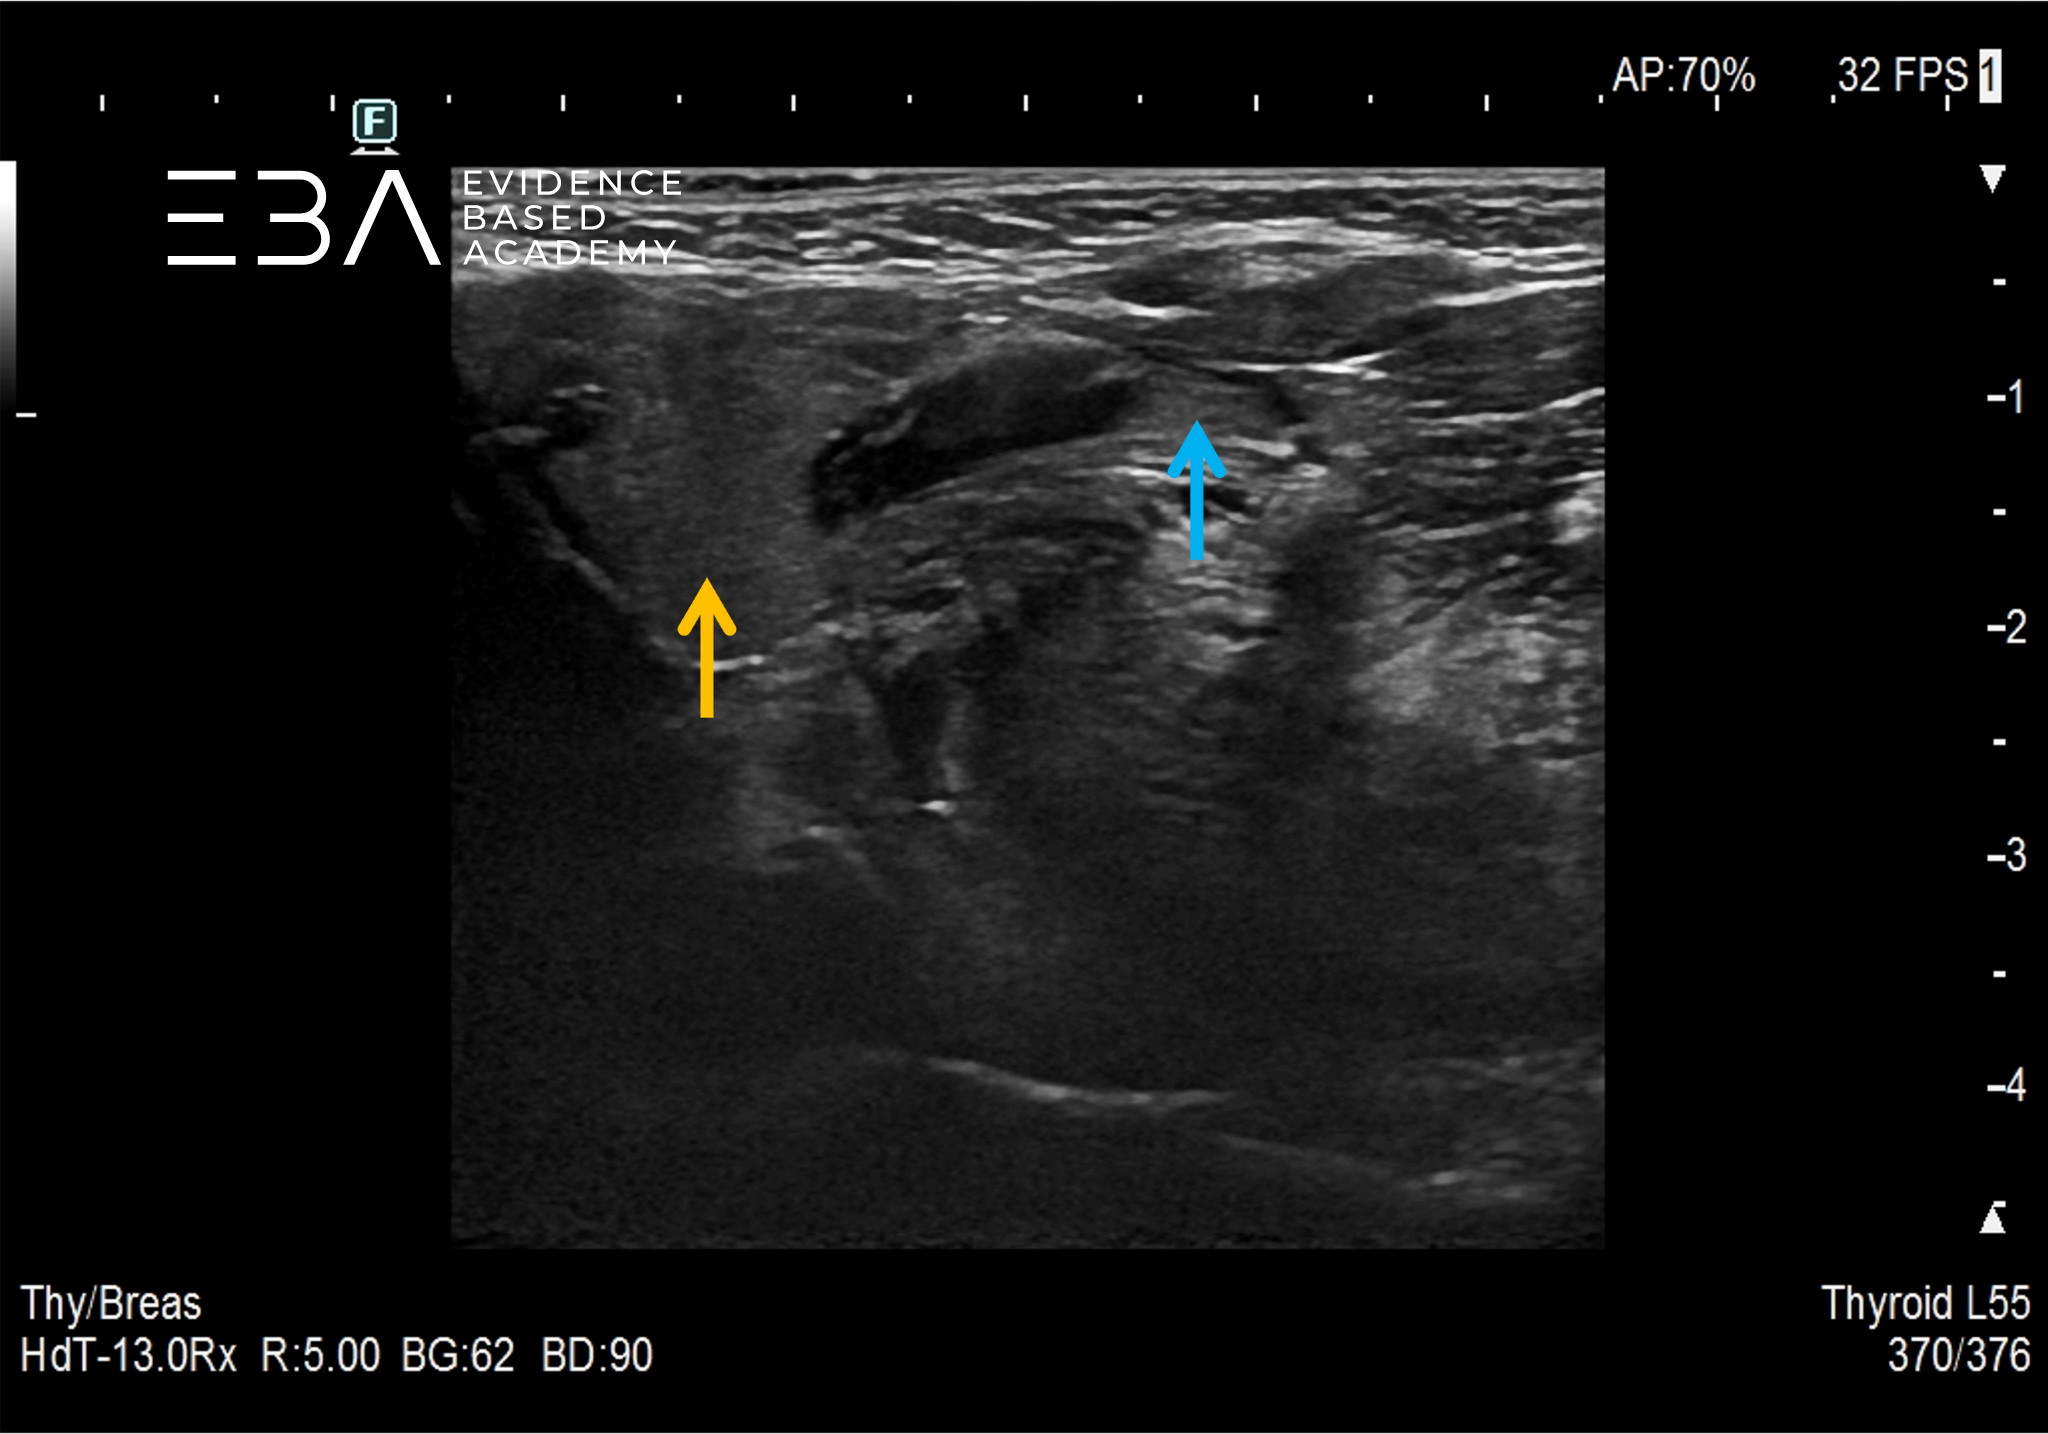

1. Porównanie echogeniczności miąższu ślinianki przyusznej (zielona strzałka) i ślinianki podżuchwowej (żółta strzałka)

USG ślinianki charakteryzują się echogenicznością wyższą od echogeniczności mięśni (zbliżoną do echogeniczności tkanki tłuszczowej oraz echogeniczności prawidłowego miąższu tarczycy) i jednorodną echostrukturą. W warunkach prawidłowych przewody wyprowadzające zazwyczaj są niewidoczne. Echogeniczność ślinianki podżuchwowej może być nieco niższa od echogeniczności ślinianki przyusznej. Unaczynienie prawidłowych ślinianek jest skąpe, a w przypadku ślinianek podjęzykowych często trudne do uwidocznienia.